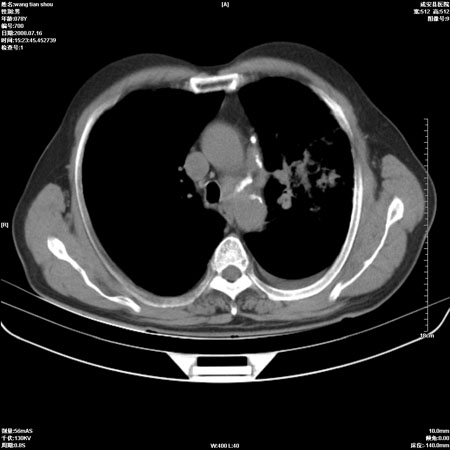

以下是引用qingjing在2008-7-16 19:55:00的发言:[br]1、左上肺不张并堵塞性炎症,建议支气管镜详查;[br]2、左侧胸腔少量积液。

以下是引用zsl6918在2008-7-17 8:09:00的发言:[br]肺炎胸膜炎可能性大,建议抗炎治疗后复查

以下是引用wzr在2008-7-16 20:26:00的发言:[br]左肺肺不张伴阻塞性肺炎!另:左侧胸腔少量积液。建议纤支镜检查!